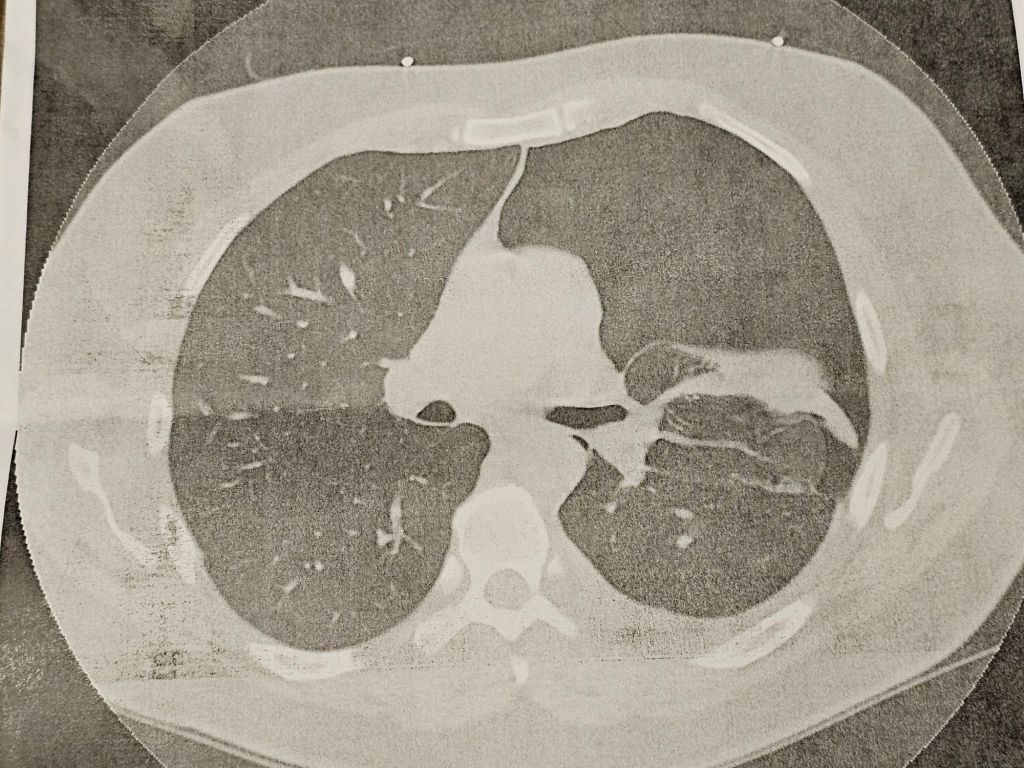

Before I got home, the doctor called me and said he didn’t see any issues in the x-ray for my gall bladder. However, around 10 p.m., he called again while we were getting ready for bed. He called both of our phones since I wasn’t picking up. I listened to the message he left telling me their radiology tech had reviewed the x-ray and noticed my left lung collapsed. As soon as I hung up, he was calling again. I answered, and he repeated the message and told me to go to the ER. So, got dressed and headed out.

I got checked in and taken back. The ER doctor acted like he wasn’t convinced that’s what was going on. They did another x-ray, and an ultrasound. Not sure, they put me through the CT. The radiologist said it would be about 30 minutes before they got results. Not even 5 minutes later, the doctor came in and confirmed that it was collapsed.

When I saw the pulmonary doctor, he wasn’t sure what caused this. His best guess was that the pulmonary embolism may have damaged the lung and created a hole.